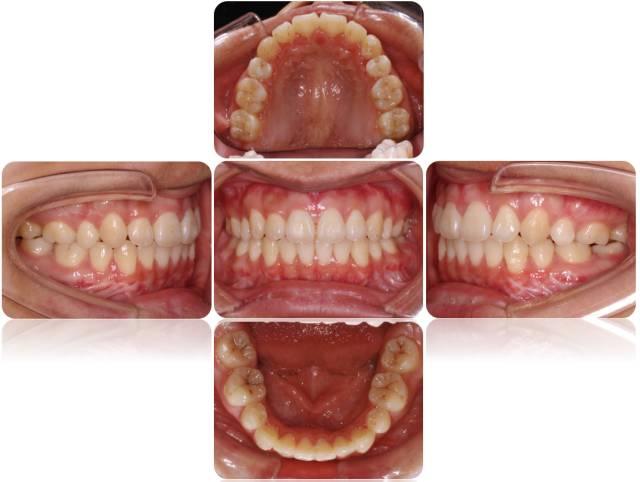

导语:正畸治疗可以改善患者牙颌面部的美观,功能和健康.

最终通过正畸将所有的牙齿"改斜归正",上颌拔除两颗双尖牙,下颌利用

隐形牙套不仅在美观度,舒适度上更有优势,而且适用于各种错颌畸形.